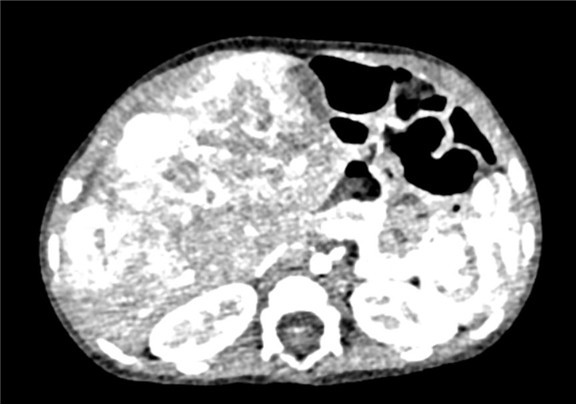

上腹部增强CT:肝脏占位性病变,疑似肝母细胞瘤,或血管母细胞瘤.

术前CT检查:

动脉期

静脉期